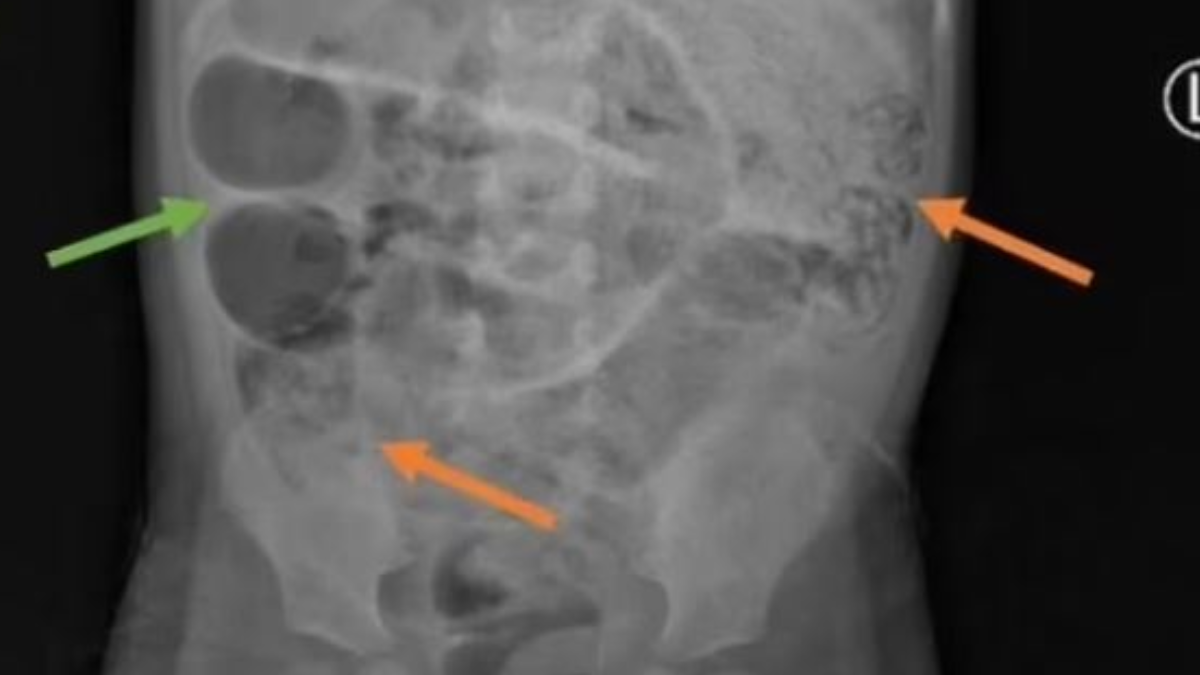

Endonezya'da aylarca mide ağrısı, kabızlık ve ateşlenme sorunu yaşayan 3 yaşındaki çocuk, bir süre sonra kurt kusmaya başladı. Karın şişliği ile hastaneye kaldırılan çocuğa röntgeni çekildi. Gri kitlelerin görüldüğü röntgende kurtların ince bağırsağın üç ayrı bölgesini tıkadığı ortaya çıktı.

Tıbbi adı Ascaris lumbricoides olarak adlandırılan bu yuvarlak solucan türü, 35 cm uzunluğa kadar büyüyebiliyor ve insan bağırsağında yaşayabiliyor. Doktorlar ise bu durumun yaşanmasındaki ihtimalin kirli su ve çıplak ayakla yürürken solucanlara maruz kaldığını söyledi.